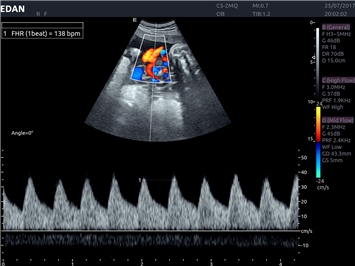

Импульсно-волновой допплер:

Да

Триплексное сканирование:

Дуплексное сканирование: